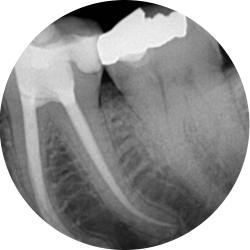

My old root filling is failing, can I get it redone?

Yes sometimes endodontic treatments are not successful for a multitude of reasons and have to be redone.

A careful assessment will be made of your tooth to see if retreatment is the best option for you. Sometimes teeth have other more significant problems that may have a significant impact on the success of the retreatment and in these cases the tooth may have to be removed.